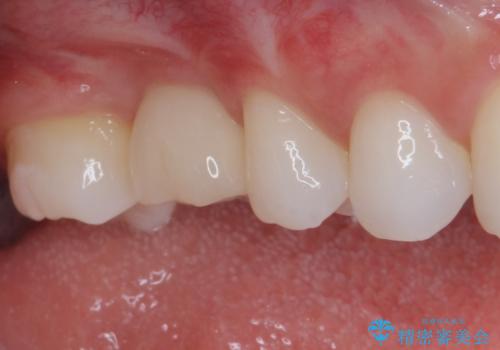

放置した奥歯の虫歯 インプラントによる欠損補綴治療

- 歯がほとんどなくなってしまうまで虫歯を放置してしまったとのことで来院された患者様です。

抜歯が必要であることは患者様自身も理解されており、インプラントによる欠損補綴治療を希望されていらっしゃいました。

その後は、オールセラミッククラウンにて補綴することとしました。